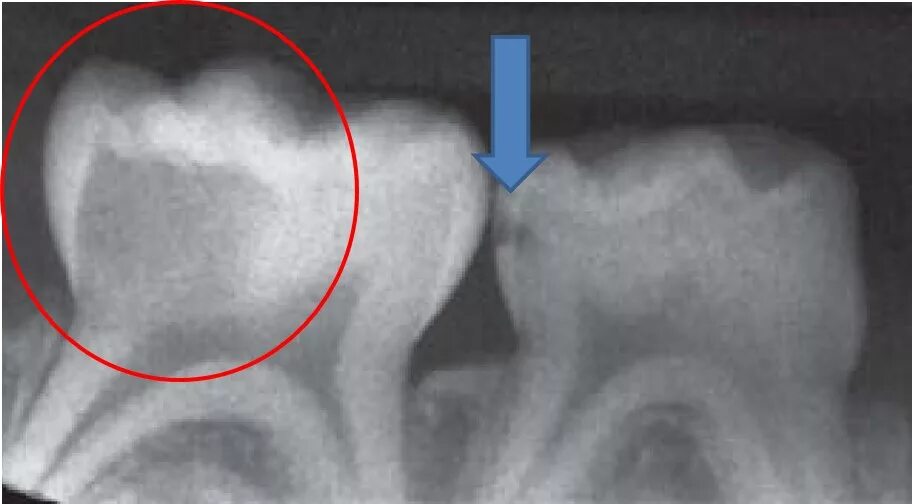

Как понять снимок зуба